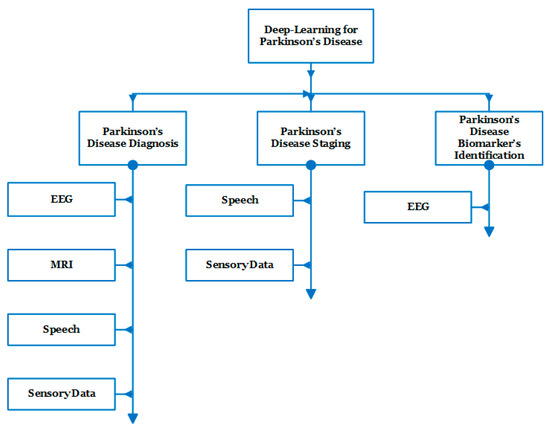

In recent studies, several dataset modalities have been exploited by efficient deep learning methods for the diagnosis of PD, staging of the disease, and the identification of biomarkers. Figure 5 shows the taxonomy of the related work that has been recently introduced during the period from 2016 to 2022 [20,21,22,23,24,25,26,27,28,29,30,31,32,33,34,35,36,37,38,39,40,41,42,43,44,45,46,47,48,49,50,51,52,53,54,55,56].

Figure 5.

Taxonomy of the related work representing the main applications as well as the main modalities used for each application.